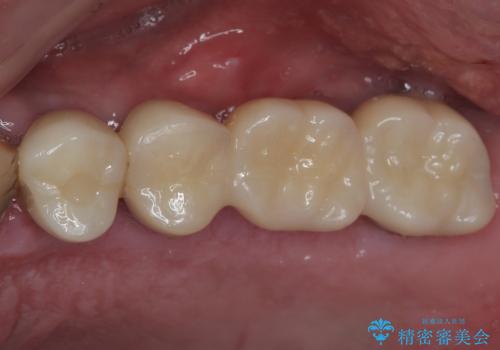

割れてしまった奥歯 抜歯即時埋入インプラントによる短期間治療

- 土台の歯が割れてしまって、歯がグラグラしているとのことで来院された患者様です。

いずれの歯も抜歯が必要な状態であり、抜歯即時埋入によるインプラント治療を行うこととしました。

右上奥歯は骨欠損の範囲が広いため、抜歯即時埋入は可能であっても、即日で仮歯を装着する即時荷重は難しいと判断されたため、手前の歯まで仮歯を装着することとしました。

術後にインプラントの安定値を測定し、十分な値が達成された後、速やかにセラミッククラウンにて補綴治療を行うこととしました。